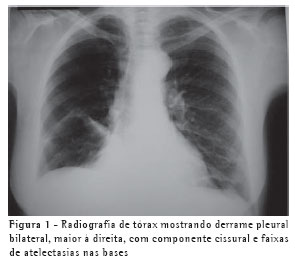

RELATO DO CASOUma mulher de 63 anos, do lar, não tabagista, previamente hígida, apresentou-se com queixa de aumento de volume em pescoço, face anterior do tórax, abdome e membros inferiores. Havia associação com dispnéia discreta aos esforços. O quadro teve início após atividade física leve em academia de ginástica, havia cinco dias. Negava doença pulmonar prévia e referia uso de fluoxetina a 20 mg/dia, bromazepam a 3 mg/dia e reposição hormonal feminina regular. Ao exame clínico observou-se um discreto aumento de volume em fossa supraclavicular esquerda e face lateral direita do pescoço. Observou-se ainda diminuição do murmúrio vesicular de forma difusa e de frêmito toracovocal em bases (direito maior que esquerdo), além de edema de parede abdominal anterior e de membros inferiores (grau I/IV). Foram solicitados hemograma, coagulograma, glicemia, creatinina, uréia, velocidade de hemossedimentação, colesterol total, HDL, triglicerídeos, T3, T4, TSH e parcial de urina, os quais se apresentaram todos normais, descartando a presença de dislipidemia, coagulopatia, infecção, nefropatia e hipotireoidismo. A avaliação radiológica do tórax revelou um pequeno derrame pleural bilateral (Figura 1), confirmado pela tomografia axial computadorizada de tórax (Figura 2A). Esta foi complementada com cortes ao nível do pescoço, que evidenciaram edema na região supraclavicular esquerda com imagem hipodensa (20 x 10 mm) adjacente ao feixe vasculonervoso do pescoço (Figura 2B). A ultra-sonografia da região cervical mostrou a formação de uma coleção cística, posteriormente aos vasos cervicais, sugestiva da ruptura do tronco jugular esquerdo. Demonstrou ainda um pequeno aumento da espessura do músculo esternocleidomastóideo esquerdo, sugestivo de processo inflamatório secundário a distensão muscular (Figura 3). A paciente foi submetida a toracocentese diagnóstica à direita com obtenção de líquido leitoso compatível com QT. A análise laboratorial demonstrou tratar-se de um exsudato com predomínio de polimorfonucleares e com dosagem de triglicerídeos de 2.035 mg/dl, colesterol de 131 mg/dl e proteínas de 9,7 g/dl, confirmando o quadro laboratorial de QT. Foram realizadas citologia oncótica, bacterioscopia de Ziehl, micológico direto e culturas, que resultaram negativos, descartando processos malignos e doenças infecciosas.